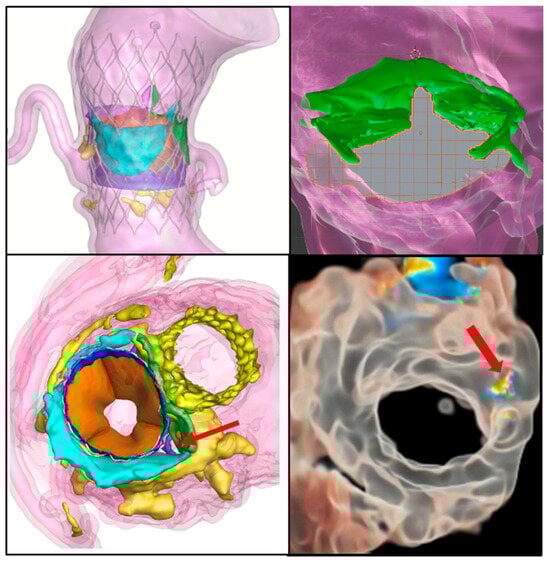

4.1.3. Paravalvular Leak

4.1.4. Percutaneous Alternatives for Coronary Artery Obstruction

4.1.7. TAVI in Bicuspid Aortic Valves

4.2.3. Native TMVR